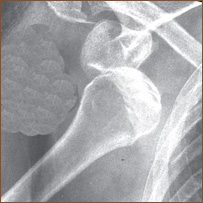

روغتيا او ژوند: د هډوکو ماتېدل او لومړنۍ مرستې

مات هډوکی

کله چې د هډوکو ترمنځ پيوستون له منځه ولاړ شي او فرق پکې راشي، دې حالت ته د هډوکو ماتېدل وايي.

د هډوکو ماتېدل دوه حالتونه لري چې، يو يې پرانيستی او بل يې هم سرپټی حالت دی.

پرانيستی حالت دې ته وايي چې دهډوکې د ماتېدو ترڅنګ د هماغې برخې پوستکی هم څيري او پرهر ځينې جوړشي .

سرپټی حالت بيادې ته وايي چې، هډوکی مات شي خو ظاهراً يې ټپ نه ليدل کېږي.